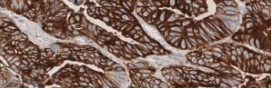

¿Cómo interpretar la tinción de CLDN18.2?

Cuando se reporta la expresión de CLDN 18.2 se deben incluir, tanto la intensidad de la tinción, como el porcentaje de las células tumorales.

En tumores G/UGE, la CLDN18.2 se reporta como el porcentaje de células teñidas con una intensidad de tinción de la membrana de moderada a intensa1.

• Muchos estudios han incluido para la puntuación de la CLDN18 exclusivamente los porcentajes de células tumorales que mostraban tinción de membrana de moderada a intensa (2+/3+).